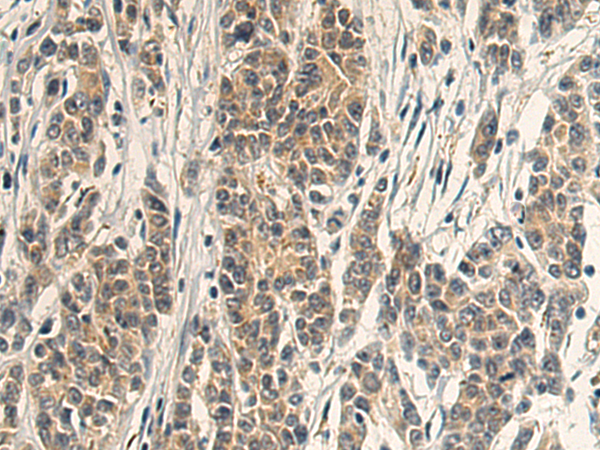

分类: 科研抗体货号: P08712别名: ARA54; HFB30; TRIAD2; HRIHFB2038应用: WB,IHC反应种属: Human, Mouse